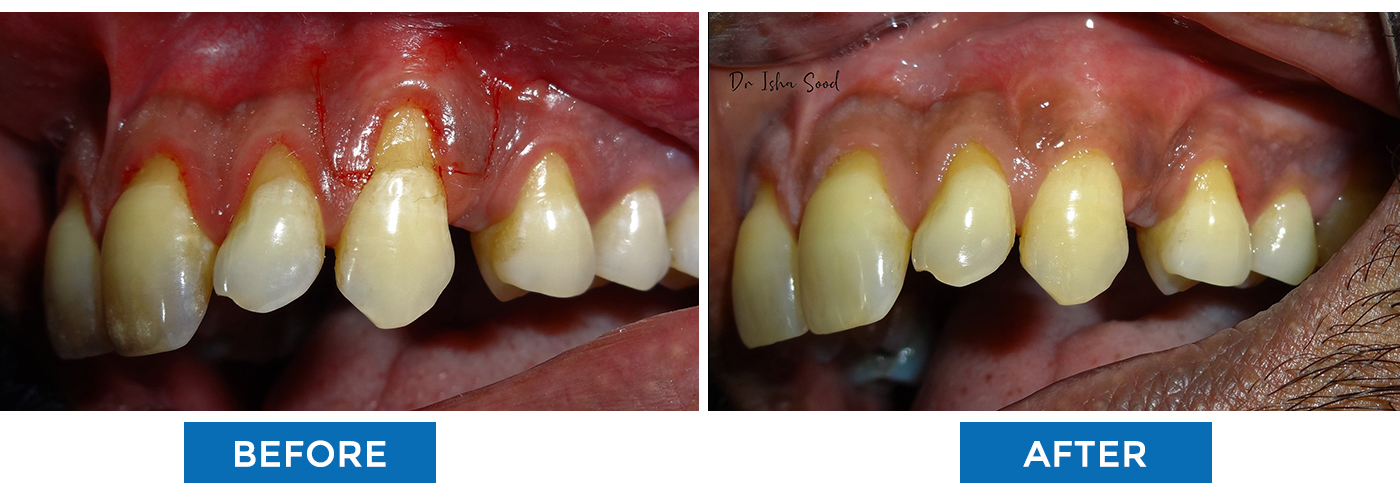

Gum Surgery To Cover The Root Of The Tooth